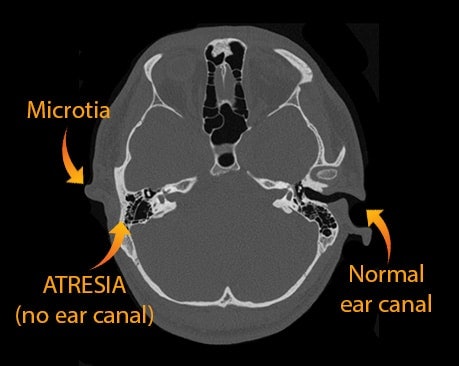

Most patients born with microtia also have "aural atresia" (lack of an ear canal). Luckily, these children usually have a normal inner ear and hearing nerve (cochlea), which means they are not deaf. Instead they have conductive hearing loss which can be treated by Dr. Bonilla as well.

Is a child with microtia deaf? In almost all cases, the answer is no. Why? During in-utero development the outer ear and middle ear form at about the same time. When there is a severe congenital malformation of the outer ear, such as a microtia, then there is usually a malformation of the middle ear as well. Most of the time, the middle ear malformation consists of fused or malformed middle ear bones, a smaller middle ear cavity and an abnormal course of the facial nerve.

In conclusion, a child with a microtia will usually have normal sensorineural hearing and moderate to severe conductive hearing loss. All this means is that the child’s inner ear is normal (normal sensorineural status), but because there is no ear canal, there is no way for sound to “conduct” to the inner ear via the ear canal. As a result, there will be conductive hearing loss.